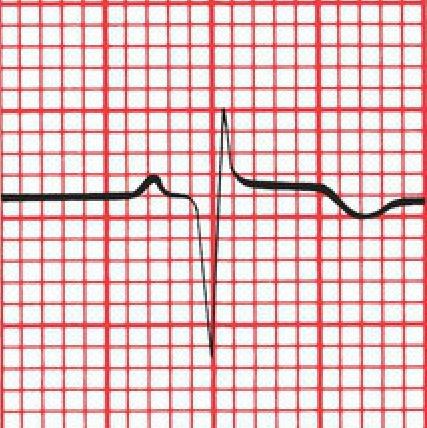

ECG: During an acute MI, ECG evolves through 3 stages (T peaking followed by T inversion; ST elevation; Appearance of Q waves)

Yet T wave inversion of MI are Symmetrical, whereas most other ones are Asymmetric, with a gentle downslope and a rapid upslope.

(A) The symmetric T wave inversion in a patient with ischemia. (B) An example of asymmetric T wave inversion in a patient with left ventricular hypertrophy and repolarization abnormalities.